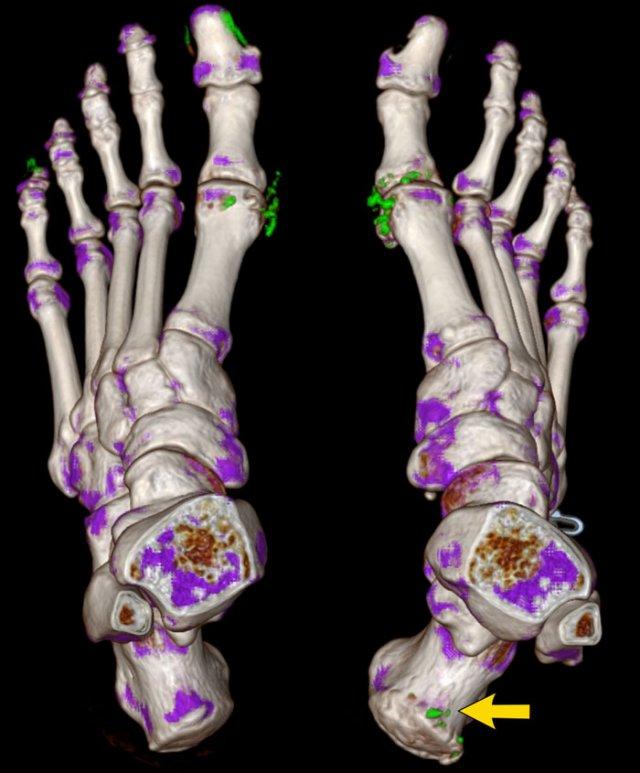

Tỷ trọng mô mềm

Sưng mô mềm tăng tỷ trọng điển hình bao quanh khớp MTP1 hai bên.

Bào mòn cạnh khớp ở mặt trong của đầu xương bàn chân (MT) phía xa, có viền xơ cứng.

Tổn thương rõ nhất ở bên phải (mũi tên).

Tiếp tục với hình ảnh CT Năng lượng kép (Dual Energy CT)…

CT Năng lượng kép (Dual Energy CT) của cùng bệnh nhân gout cho thấy các vùng lắng đọng tinh thể urat.

Trong hình tái dựng 3D này, các vùng lắng đọng tinh thể được mã hóa màu xanh lá và có thể thấy bao quanh các khớp MTP và tại điểm bám của gân Achilles bên phải (mũi tên).

Các điểm ảnh màu xanh ở giường móng của ngón 1 và ngón 5 bên trái là xảo ảnh do keratin trong móng dày.

CT Năng lượng kép là phương pháp không xâm lấn để phát hiện tinh thể urat, có thể thay thế chọc hút dịch khớp.

Một trường hợp khác với hạt tophi điển hình và bào mòn cạnh khớp trên phim X-quang thường.

CT Năng lượng kép cho thấy tín hiệu gout tại khớp MTP1, MTP2 và các khớp liên đốt ngón của ngón 3.

DECT hữu ích cho chẩn đoán khi các dấu hiệu không điển hình.

Phương pháp này cũng rất hữu ích để đánh giá mức độ lan rộng của bệnh.

Trong trường hợp này, ban đầu nghi ngờ u xương.

Có một số dấu hiệu có thể gợi ý chẩn đoán u xương tạo xương (osteosarcoma) hoặc u sụn (chondrosarcoma).

Tuy nhiên, trường hợp này đã được xác nhận là gout.

Tiếp tục với hình ảnh DECT…

Với các hình ảnh DECT này, không còn ai nghi ngờ về chẩn đoán nữa.